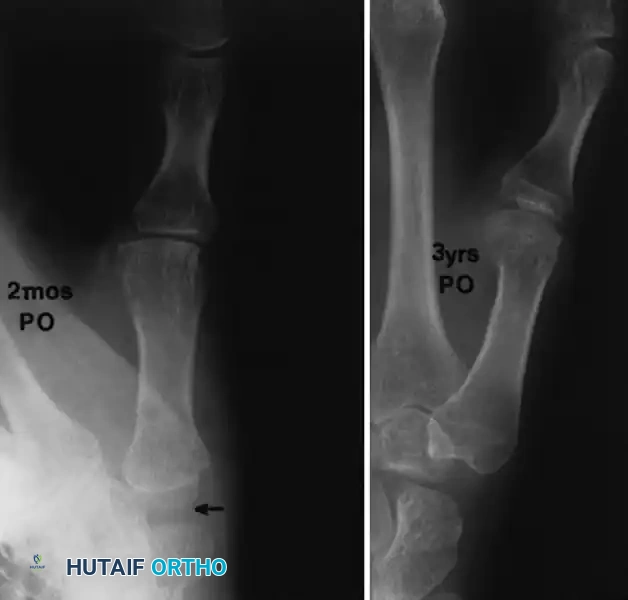

Radiographic Outcomes of Trapeziometacarpal Procedures

When simple trapezium excision is performed without robust ligamentous suspension, proximal migration (settling) of the first metacarpal is a known biomechanical consequence.

FIGURE 73-35: Radiographic progression at 2 months and at 3 years after simple trapezium excision (arrow). Note the progressive metacarpal settling and resultant scaphometacarpal space narrowing; however, clinically, the thumb often remains functionally stable despite this radiographic appearance.